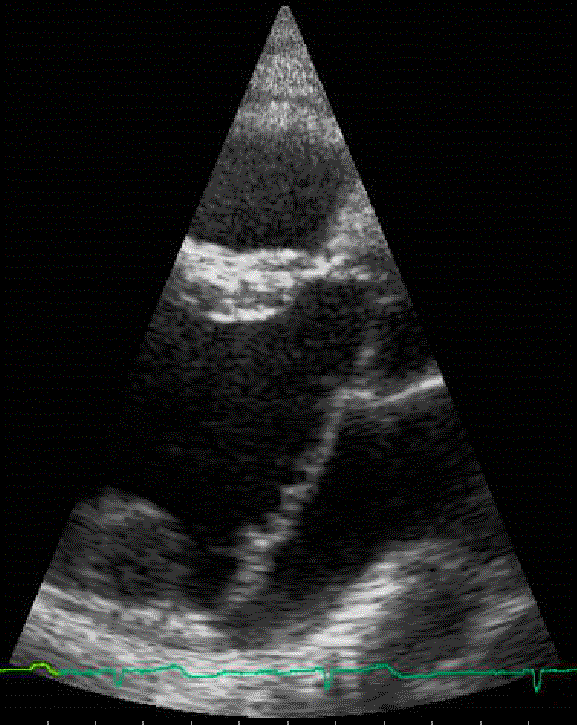

The

echocardiogram was performed at a local heart center. It

looked like a sophisticated version of the ultrasound

that was performed on expectant mothers - but with doppler

imaging so parameters such as blood flow

aspects can be determined.

I

was able to watch the echo during the whole procedure.

The inside of the heart, the valve movement, etc, was all

clearly visible. Not knowing what to look for, I would